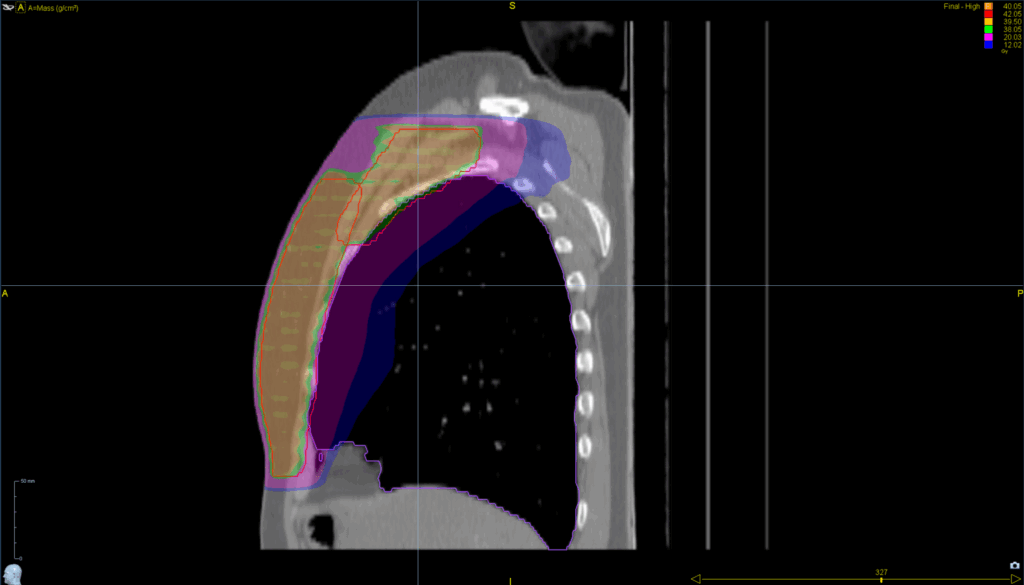

Treatment Plan Images

Treatment Planning Highlights

Fractionation / Protocol Used

40.05 Gy in 15 fractions

PTV(s) Volume

23.2 cm

Mode

- Tomohelical™

- TomoEDGE™ 5 cm

Planning Time Optimized with VOLO™ Ultra

60 min